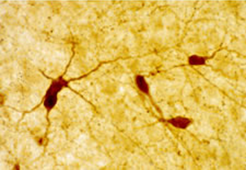

In rat central nervous system, the antiserum has significant staining with a very low background at a 1/5,000 –1/10,000 dilution using the Biotin-Streptavidin/HRP detection method. All staining is blocked by preabsorption of the diluted antiserum with excess NPY. Cross reactivity experiments in which diluted NPY antiserum was absorbed with excess peptide YY, avian pancreatic polypeptide, B-endorphin, vasoactive intestinal peptide, cholecystokinin or somatostatin showed no affect in blocking the intensity of staining.

Background Neuropeptide Y (NPY) is a member of a regulatory peptide family and has marked sequence homology with pancreatic polypeptide (PP) and peptide YY (PYY), which are other members of the family. In the rat central nervous system, immunohistochemistry has found NPY-like cell bodies in the cortex, caudate-putamen, hypothalamus (arcuate nucleus), hippocampus, anterior olfactory bulb, nucleus accumbens, amygdaloid complex and periaqueductal grey. NPY-like fibers and terminals are detected in high numbers in the bed nucleus of the stria terminalis, the peri- and paraventricular regions of the hypothalamus and thalamus and in discrete hypothalamic nuclei, particularly the suprachiasmatic nucleus.